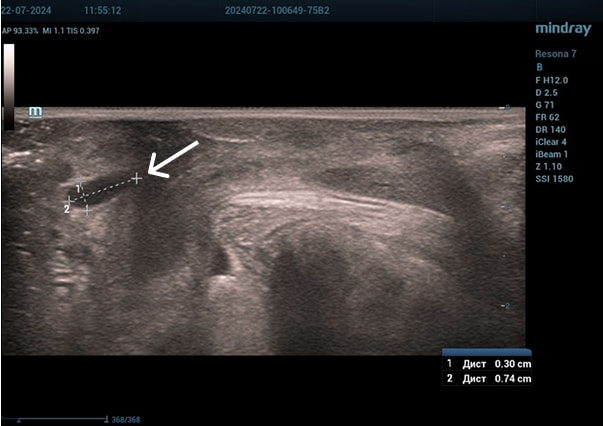

Эхограммы периуретральной области

Трансперинеальный доступ, линейный датчик.

Слева от уретры округлое образование с четкой капсулой и мелкодисперсной взвесью размерами 1,5×1,0 см (филлер с воспалением), справа — анэхогенное овоидное образование (филлер).

Трансперинеальный доступ, конвексный датчик.